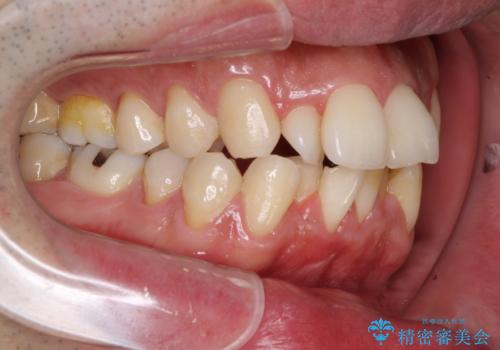

下顎骨が顕著な左右差を持って成長したため、右側にずれている状態でした。

この方は元々骨格的な偏位が大きかったためか、治療中に下顎骨が上顎骨よりも右外側に誘導されて、右側の奥歯が全く咬合しない状態が続いてしまいました。

最終的にはゴムかけなどを活用して改善することができましたが、4年近い治療期間を要することとなりました。